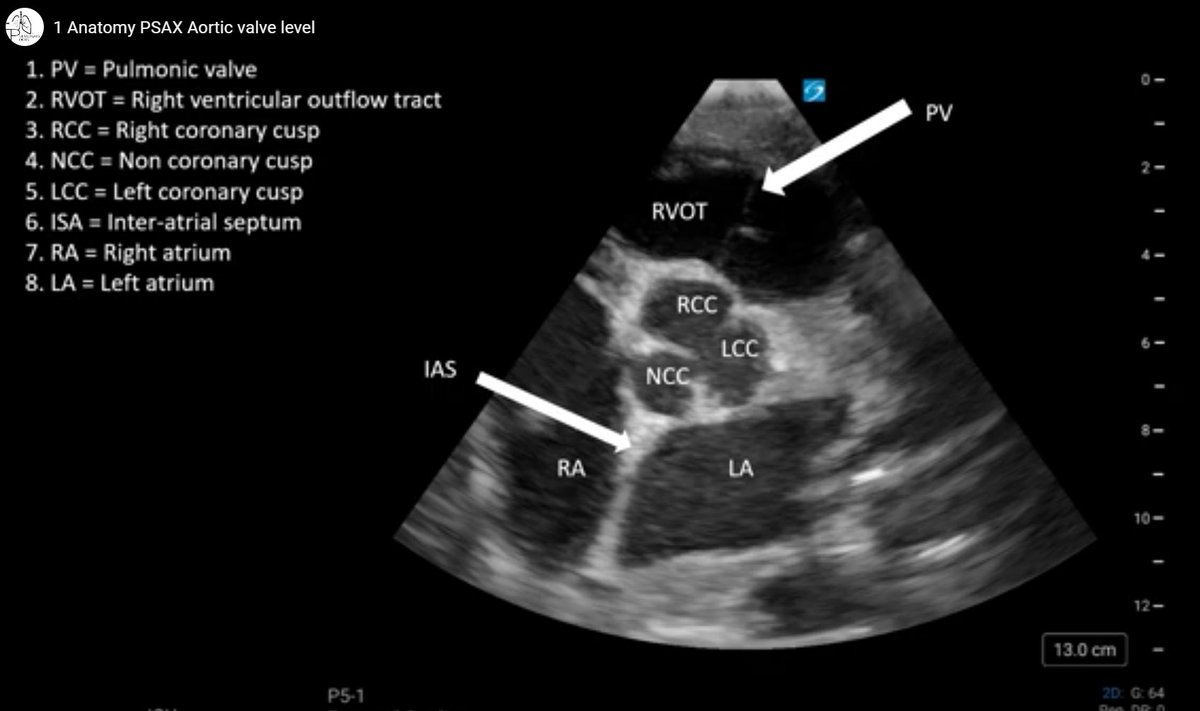

We did inflow, now it's time for outflow.IU Pulmonary and Critical Care Fellowship